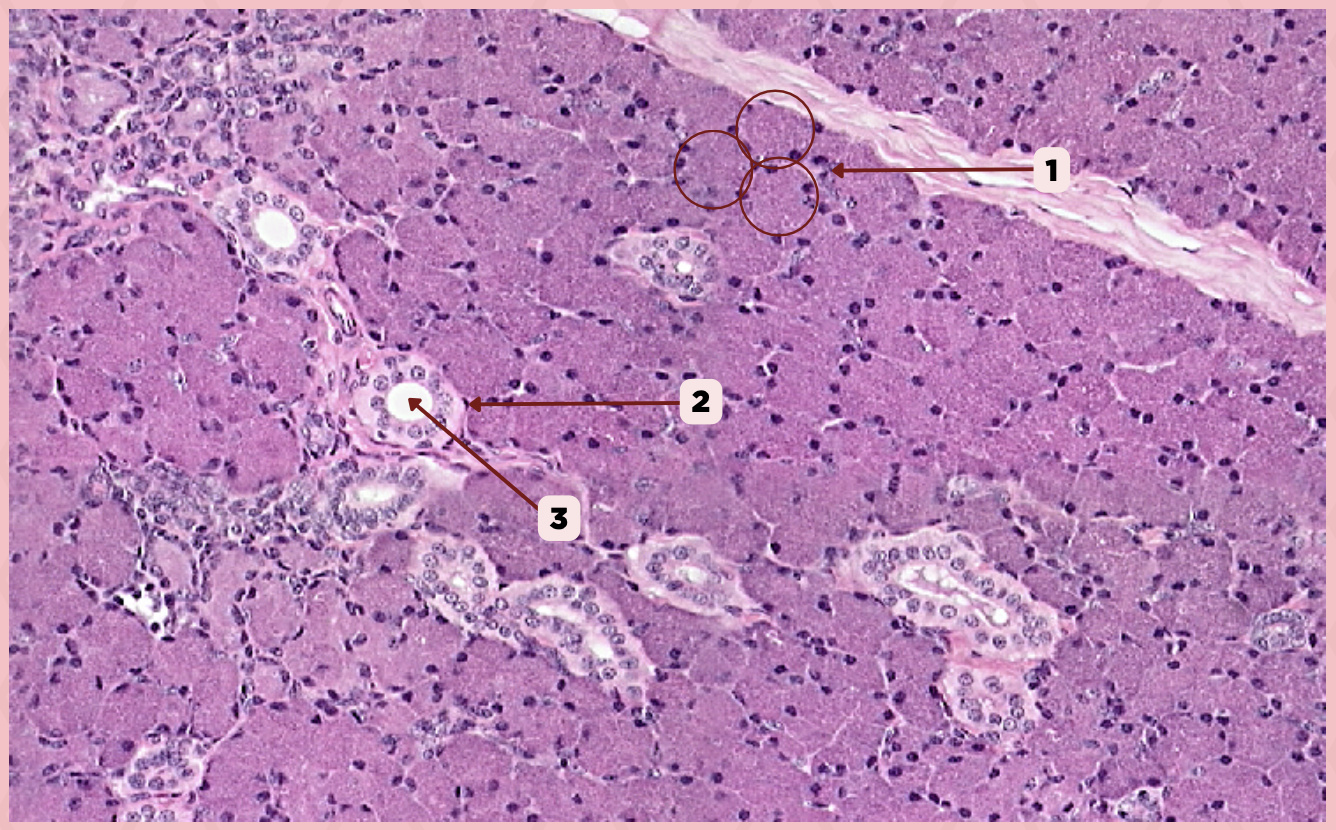

Parotid

Identify the specimen.

Secretory Acini

Identify the structure labeled as 1.

Myoepithelial Cell

Identify the structure labeled as 2.

Secretory Duct

Identify the structure labeled as 3.

Parotid

Identify the specimen.

Capsule

Identify the structure labeled as 1.

Lobule

Identify the structure labeled as 2.

Lobe

Identify the structure labeled as 3.

Connective Tissue

Identify the structure labeled as 4.

Parotid

Identify the specimen.

Adipocyte

Identify the structure labeled as 1.

Connective Tissue

Identify the structure labeled as 2.

Intercalated Duct

Identify the structure labeled as 3.

Striated Duct

Identify the structure labeled as 4.

Serous Gland

Identify the structure labeled as 5.